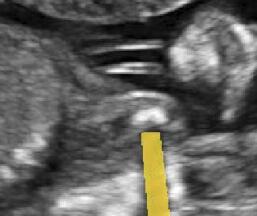

We integrate our shadow confidence maps into an automatic biometric measurement approach [32], and show the biometric measurement performance (measured by DICE) before and after adding shadow confidence maps.

Similar to the ultrasound standard plane classification, shadow confidence maps are integrated into a biometric estimation model described in [32] as an extral channel. Specifically, we train and test four fully convolutional networks with the same hyper-parameters as detailed in [32], and use the same ellipse fitting algorithm described therein. The first network is trained only on the image data used in [32]. The other three networks are trained with an additional input channel for shadow confidence maps that are separately generated by the baseline, the proposed, and the proposedAG method.

We show three examples that are affected by shadows, and show their biometric measurement results in Table V. From this experiment, we find that biometric measurement performance is boosted by up to for problematic failure cases after adding shadow confidence maps. The average performance on the entire test data set stays almost the same since only a small proportion of the test images are affected by strong shadows, mainly because of the image acquisition by highly skilled sonographers.